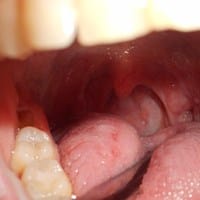

Sensación de tener algo dentro de la nariz y amígdala izquierda inflamada.

Acudo a ustedes porque ya no sé que hacer, os cuento un poco mi problema desde mayo del año pasado empecé con este "calvario", y es que llevo desde ese tiempo me sale el moco muy blanco y seco además tengo la sensación de tener algo dentro de la...

Acudo a ustedes porque hoy he ido a recoger una analítica que me hice porque tengo molestias en la parte izquierda de la garganta ( sobre la zona de la amígdala) y he ido ya 3 veces al otorrino y no me ve nada anormal pero sigo teniendo esa molestia,...